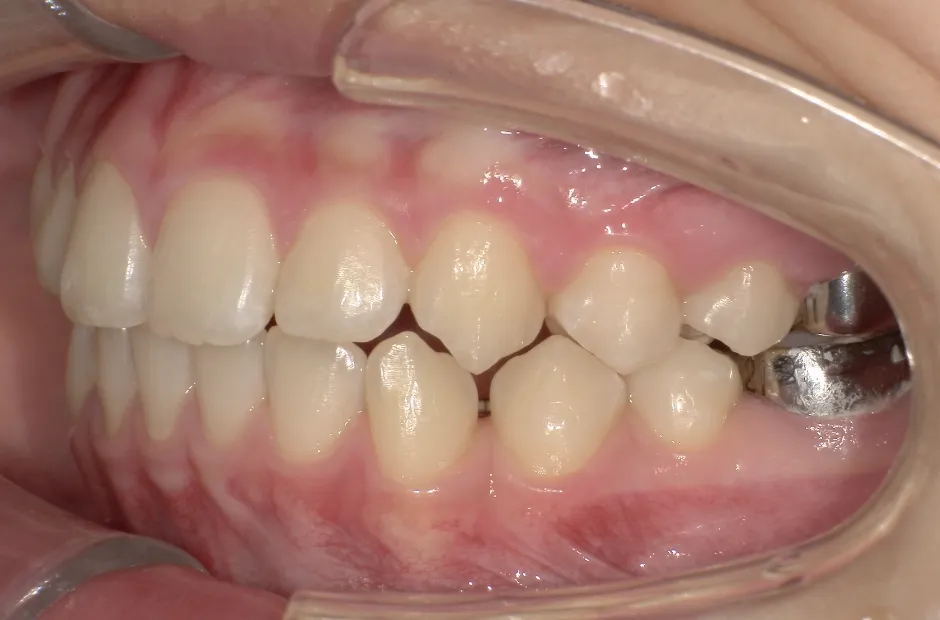

反対咬合

| 診断名・主訴 | 前歯反対咬合 |

|---|---|

| 年齢・性別 | 12歳・男性 |

| 治療期間・回数 | 1年半 18回 |

| 治療に用いた主な装置 | リンガルアーチ(前方誘導弾線) |

| 抜歯部位 | なし |

| 治療費 | 35万円(税抜) |

| リスク・副作用 | 装置による違和感・疼痛・歯肉退縮・歯根吸収・虫歯のリスクなど |

治療後